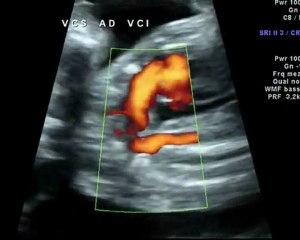

Aneurisma dell'arco aortico, a Modena protesi mai vista in Italia